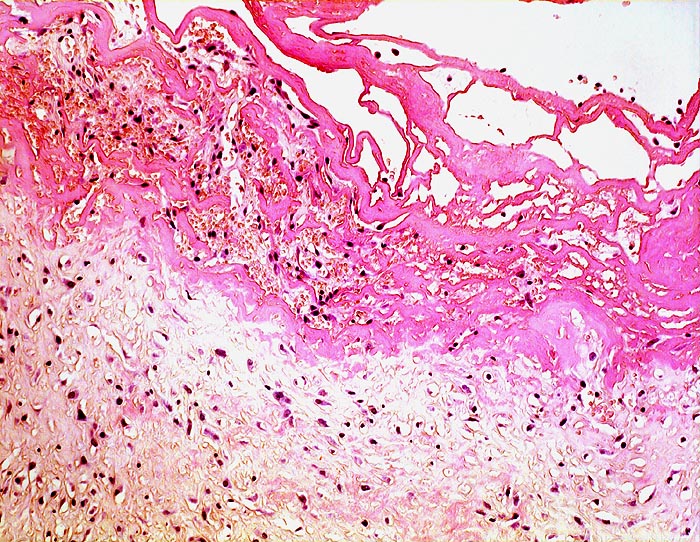

Morphologische Merkmale:

• Eröffnete Bursa mit plumpen Zotten mit kompakten Auflagerungen von hypereosinophilem Fibrin.

• Innenauskleidung durch eine Schicht flacher Synoviozyten.

• Daran angrenzend gefässreiches Granulationsgewebe mit lumennahen Erythrozytenextravasaten und Narbengewebe.

• Weiter aussen folgt Fettgewebe mit breiten Bindegewebssepten.